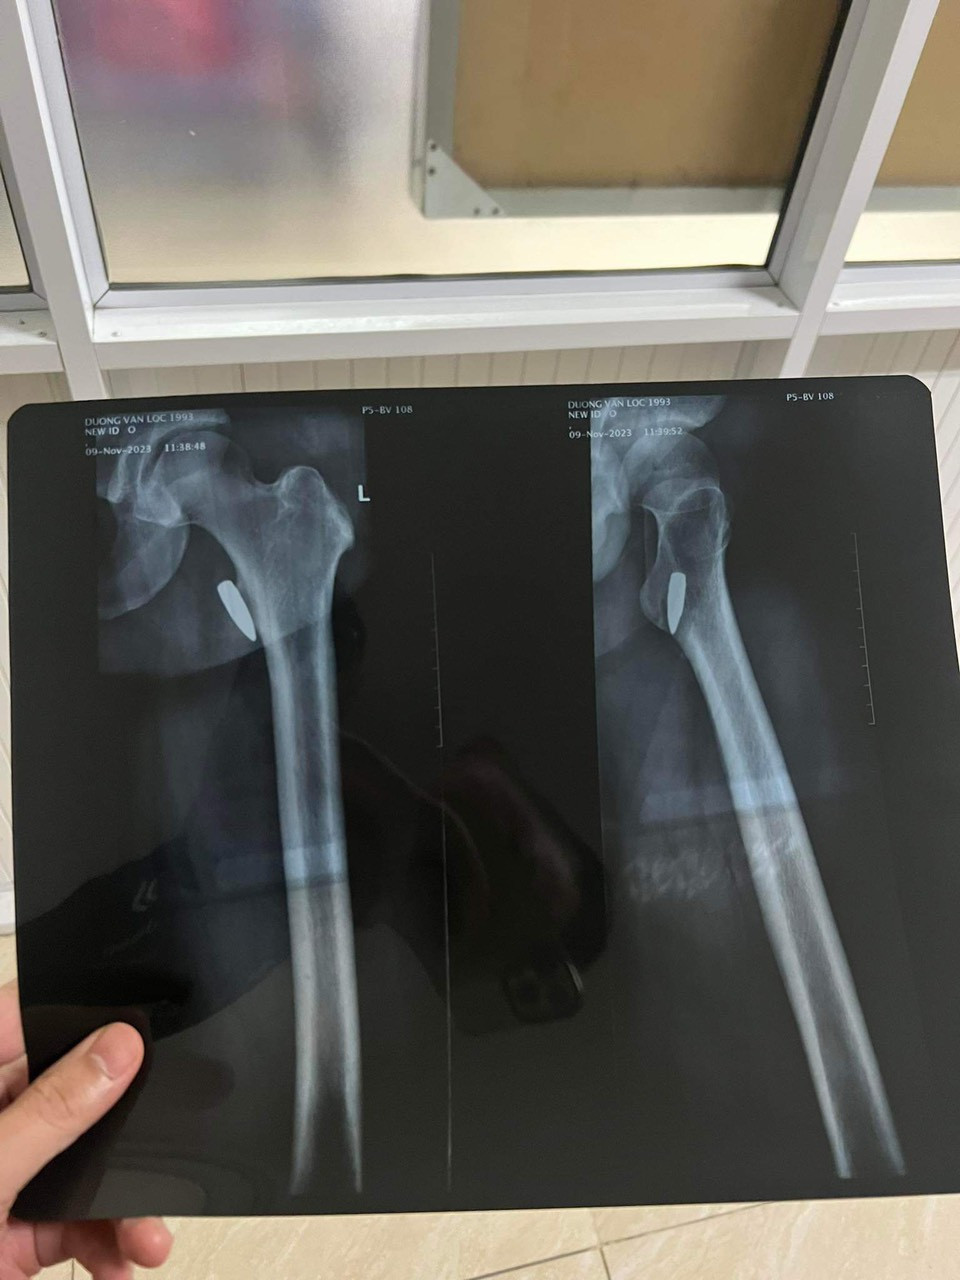

| Anh Lộc phẫu thuật để gắp đầu đạn nằm trong đùi từ năm 2017. |

Ngày 30/11, sau khi phẫu thuật để lấy viên đạn ra khỏi người, anh Dương Văn Lộc (SN 1993, trú huyện Ba Vì, TP Hà Nội) là VĐV Pencak silat tỉnh Vĩnh Phúc đã làm đơn gửi cơ quan công an tỉnh Vĩnh Phúc đề nghị tiếp tục làm rõ vụ đang đi đường bị trúng đạn năm 2017 mà báo chí từng đưa tin.

Đến ngày 15/11/2023, anh thực hiện phẫu thuật tại bệnh viện TW Quân đội 108 Hà Nội để lấy viên đạn ra, ca phẫu thuật diễn ra thành công. Hiện, anh đã gửi đơn đề nghị tới cơ quan chức năng có thẩm quyền tiếp tục điều tra làm rõ, truy nguyên nguồn gốc của viên đạn và trả lại công bằng cho anh Lộc theo quy định của pháp luật. Anh Lộc cho biết, ngoài đơn anh cũng gửi kèm cả đầu đạn cho cơ quan chức năng để phục vụ công tác xác minh, điều tra.